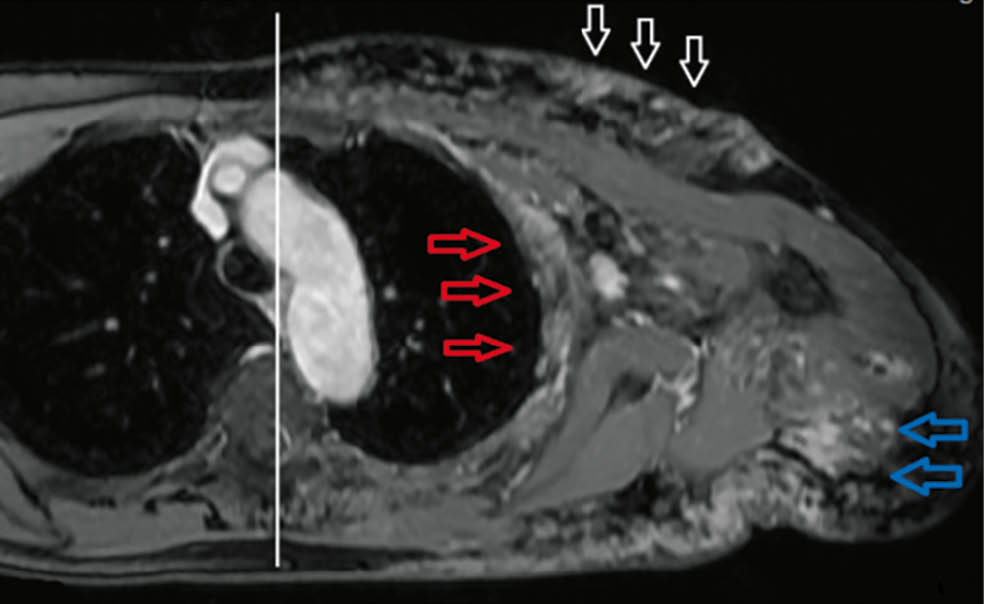

Abb. 3: KM-verstärkte fettunterdrückte axiale T1-Sequenz:

Tubulär-granuläre KM-anreichende Befunde mit Beteiligung der Interkostalmuskulatur (rote Pfeile), der Oberarmmuskulatur (blaue Pfeile) und der Kutis (weiße Pfeile). Auffällige Begrenzung der Malformation auf einen Quadranten des Körperstammes

(siehe weiße Mittellinie)